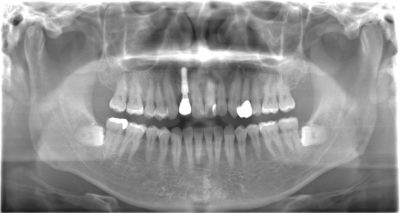

2020年 11月 22日インプラントと審美歯科の症例集が増えました。 みなさんこんにちは。藤沢市鵠沼海岸にある歯医者、医療法人社団 くげぬま海岸歯科クリニックです。 どこがインプラントだと思いますか? 答えは、左上2番目の前歯です。 インプラントと審美歯科の症例集が増えました。 興味のある方はこちらをご覧下さい。 https://www.kugenumadental.com/cases/ この記事を書いた人 院長 くげぬま海岸歯科クリニック 院長の三浦 陽平です。何歳になってもしっかり噛めるように、すてきな笑顔でいられるように、20年後・30年後を見据え、やり直しがない本当に良い治療を提供していきたいと思っています。 院長の投稿一覧 \ この記事をシェアする / 𝕏 LINE P < 前の記事 次の記事 > インプラント 審美歯科(セラミック治療)